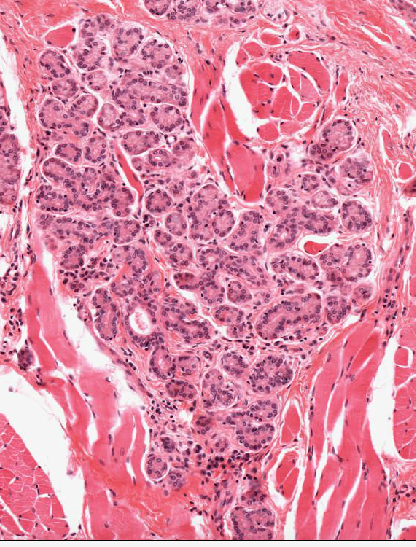

This has been taken from the tounge. What is it?

A small serous salivary gland